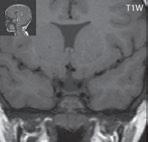

Zobrazení

Pozorujeme, že povrch mozku je plochý, nebo jsou jeho gyry a sulky výrazně redukovány, ale mohou být současně i zobrazeny oblasti (více frontálně), kde mohou být patrné ploché gyry a mělké sulky. Pod mozkovou kůrou, která je nápadně tenká, lze diferencovat vrstvu bílé hmoty, která odděluje mozkovou kůru od silné, vnitřní vrstvy šedé

hmoty mozkové. Hypogeneze corpus callosum, hypoplazie mozkového kmene z redukce počtu kortikospinálních a kortikobulbárních vláken. Dle genetiky se někdy ještě dále lissencefalie rozdělují, např. LIS1 má nejvíce postiženu oblast parietookcipitální, u X-LIS (X-vázaná lissencefalie, DCX) převažuje postižení oblastí frontotemporální.

Obr. I.1.4e Tenká mozková kůra (šipka), vrstva bílé hmoty (přerušovaná šipka), která odděluje kůru od silné subkortikální šedé hmoty (černá šipka), lissencefalie typ I

Obr. I.1.4f Tenká mozková kůra (šipka), vrstva bílé hmoty (přerušovaná šipka), která odděluje kůru od silné subkortikální šedé hmoty (černá šipka), lissencefalie typ I; stejný pacient jako na obr I 1 4e